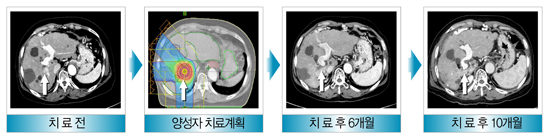

간세포암종의 양성자 치료 사례